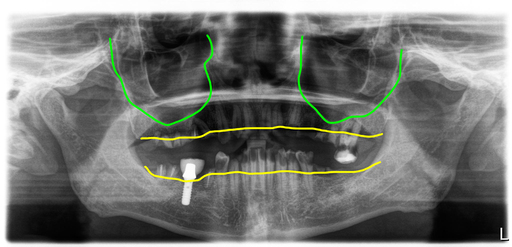

미국 델라웨어에 거주하시는 분으로 한국으로 임플란트 치료를 받으러 오셨어요. 10년 전에 미국에서 임플란트 한 개 치료 받으시고 치아관리를 제대로 하지 않았고, 콜라를 자주 드셨다고 합니다.

전체 치아가 모두 치아우식증, 즉 충치로 뿌리만 남은 치아도 많고 머리가 있다고 해도 곧 머리가 부러져 나갈 지경이었습니다.

치아우식증으로 대부분의 치아가 뿌리만 남음

콜라를 많이 드셔서 일까요? 이렇게 모든 치아가 다 썩어서 망가지기도 어렵지 않겠나 싶은데아무튼 임플란트 1개를 제외하고 모든 치아가 다 썩어서 망가져 있었어요.

그래서 결국 모든 치아를 제거하고 전체임플란트로 치료하기로 했고, 예전에 심은 임플란트는 이용해서 마무리하기로 했습니다.